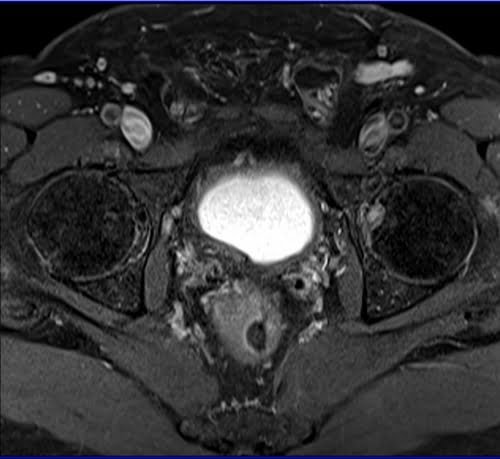

Prostatectomy patients prostate MRI T1 fat sat post contrast axial high resolution images